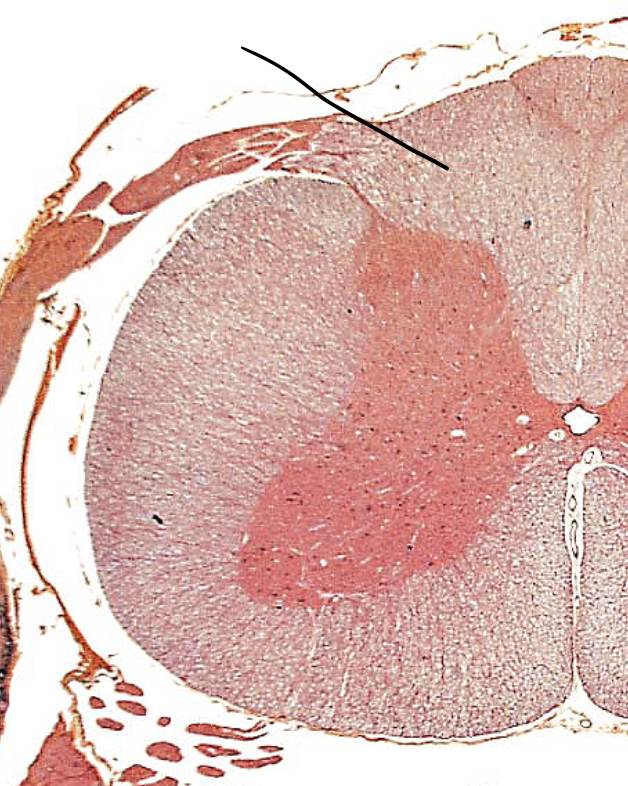

Anterior (ventral)

Posterior (dorsal)

gray horns

what is the red butterfly called

anterior gray horns

floor of grey horns

lateral gray horns

middle of gray horns

posterior gray horns

ceiling of gray horns

white columns

each side of the spinal cord has three funiculi (columns): dorsal (posterior) funiculus, lateral funiculus, and ventral (anterior) funiculus, which are further divided into tracts

anterior funiculi

floor of white column

lateral funiculi

middle of white column

posterior funiculi

ceiling of white columns

central canal

A tiny channel found within the spinal cord and inferior medulla oblongata

gray commissure

connects masses of gray matter; encloses central canal

white commissures

connects the white matter of the right and left sides of the spinal cord

anterior median fissure

a groove along the anterior midline of the spinal cord that incompletely divides it into symmetrical halves

posterior median sulcus

a shallow vertical groove dividing the spinal cord throughout its whole length in the midline posteriorly.